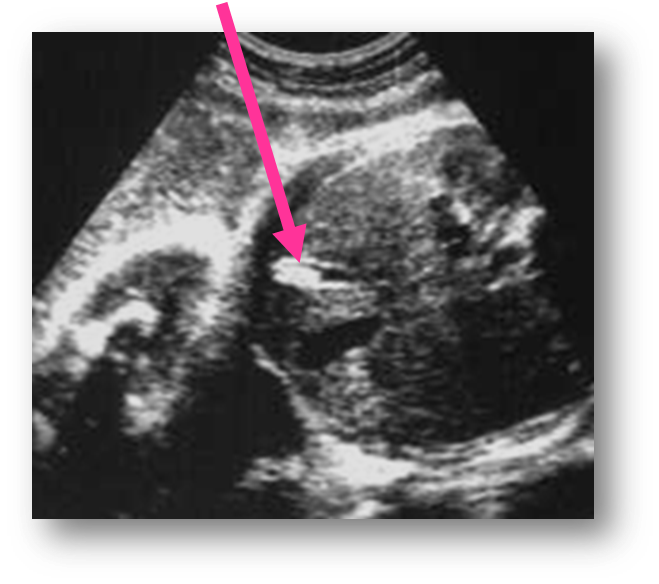

What view is this?

4 chamber view